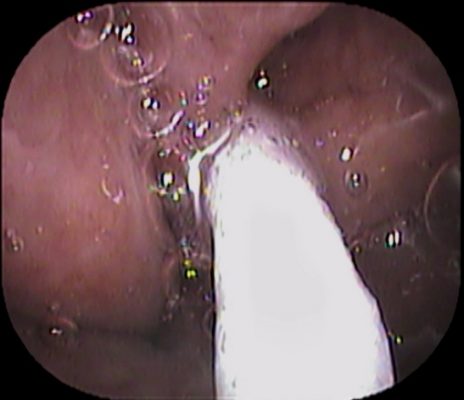

まずは鼻👃からスタートです↓

![IMG_9914[1]](https://www.inoue-ent-cl.jp/webcms/wp-content/uploads/2022/11/IMG_99141-e1667716338282.jpg)

上咽頭中央に凹みがあり、やわらかい組織でした↓

軟らかい組織で綿棒で擦ると 白い膿が出て出血しました↓

最終的にかなりの出血量に![]()